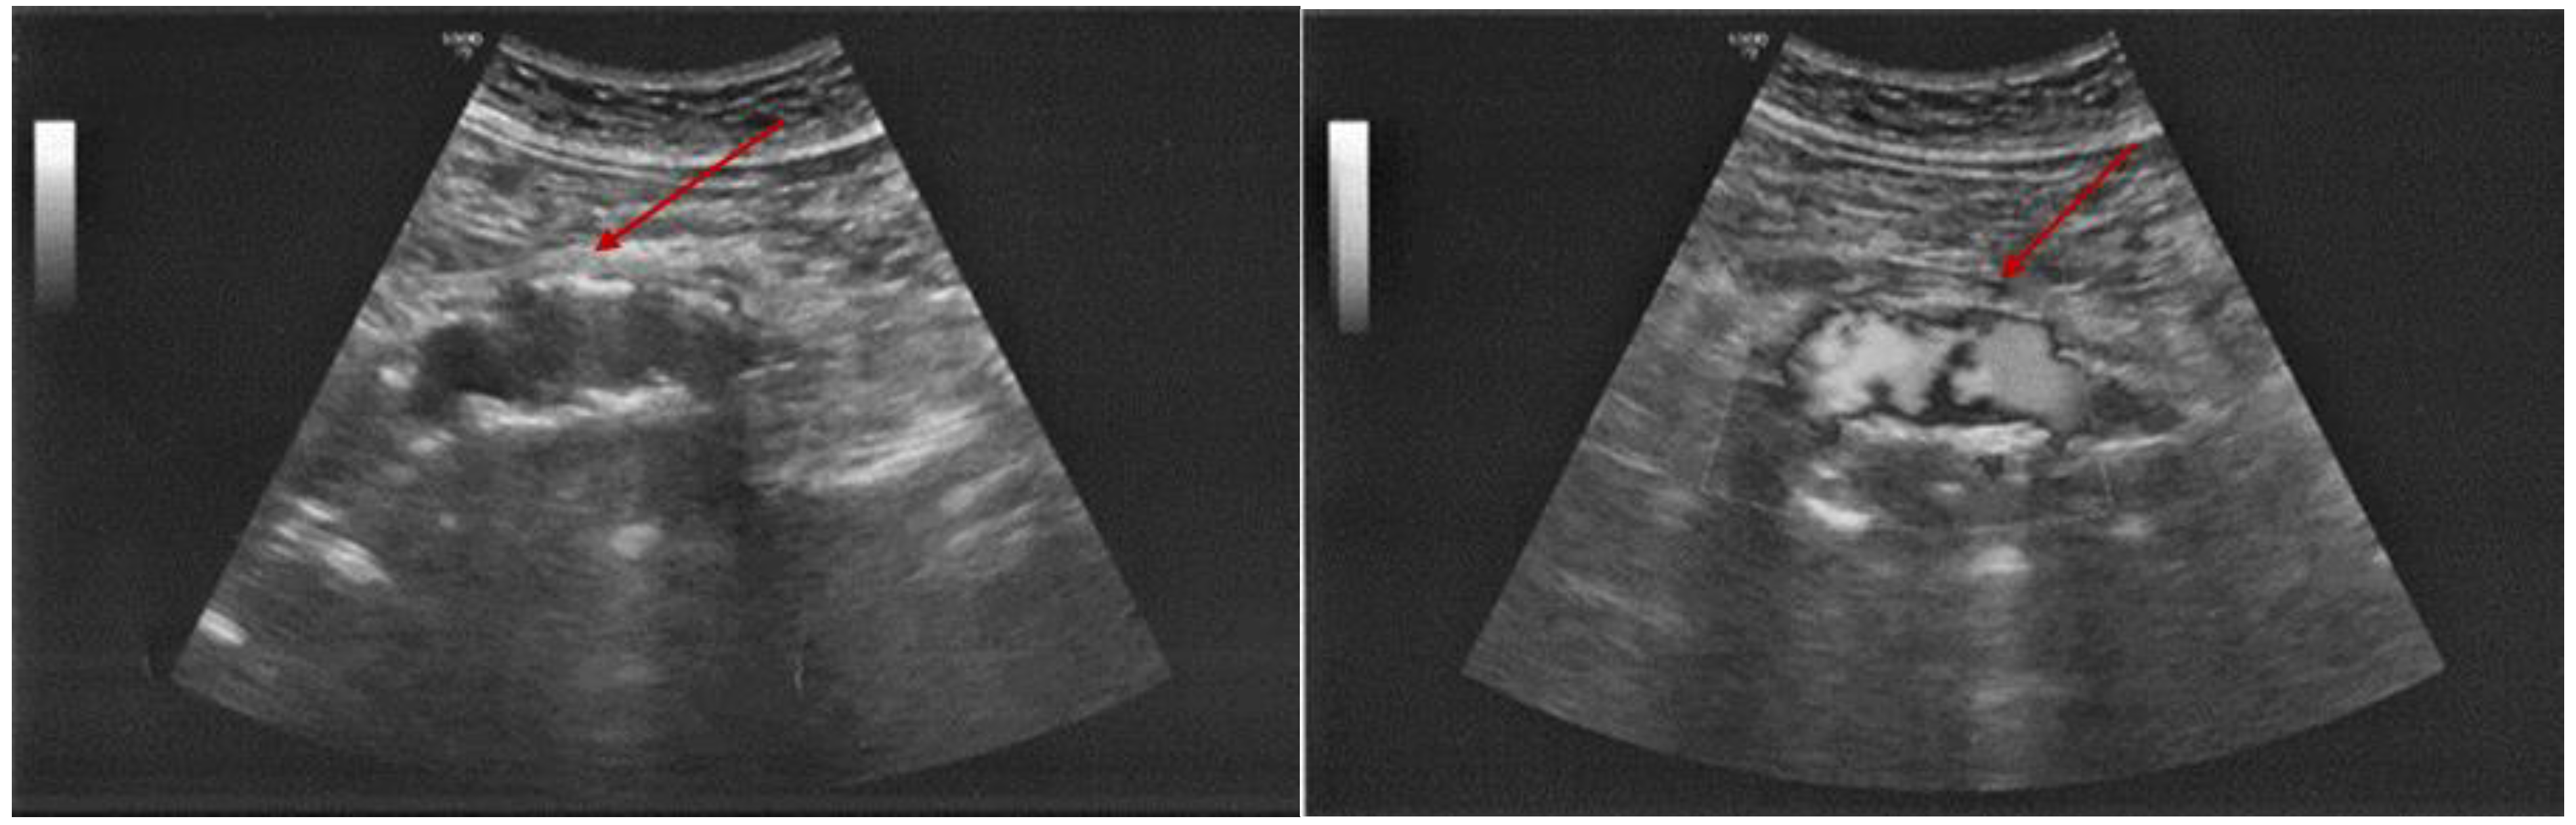

3.2.2. Additional Imaging Assessments

- Anghel, A.; Stanciu, S.; Ciobica, M.L.; Stoicescu, D.; Muresan, M.M. Contrast-enhanced ultrasound-clinical applications. Rom. J. Mil. Med. 2011, 114, 25–30. [Google Scholar]

- Stanciu, S.; Enciu, C.; Raduta, I.; Stoicescu, D.; Anghel, A.; Anghel, D.; Olan, B.; Ciobica, L. The role of contrast-enhanced ultrasound in risk assessment of carotid atheroma. Rom. J. Mil. Med. 2016, 119, 9–11. [Google Scholar] [CrossRef]